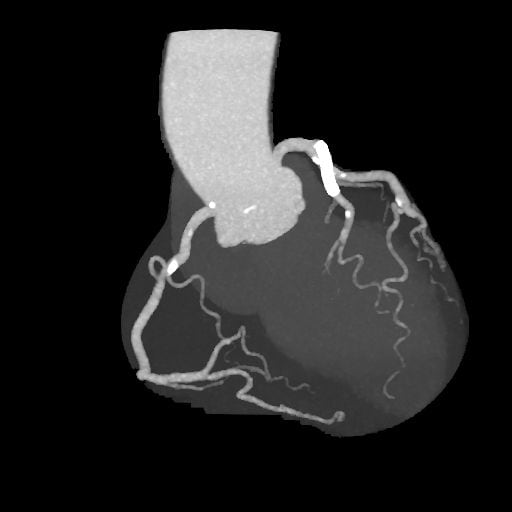

図3.アンギオグラフィックビュー

良好に造影されている。冠動脈に有意狭窄なし。